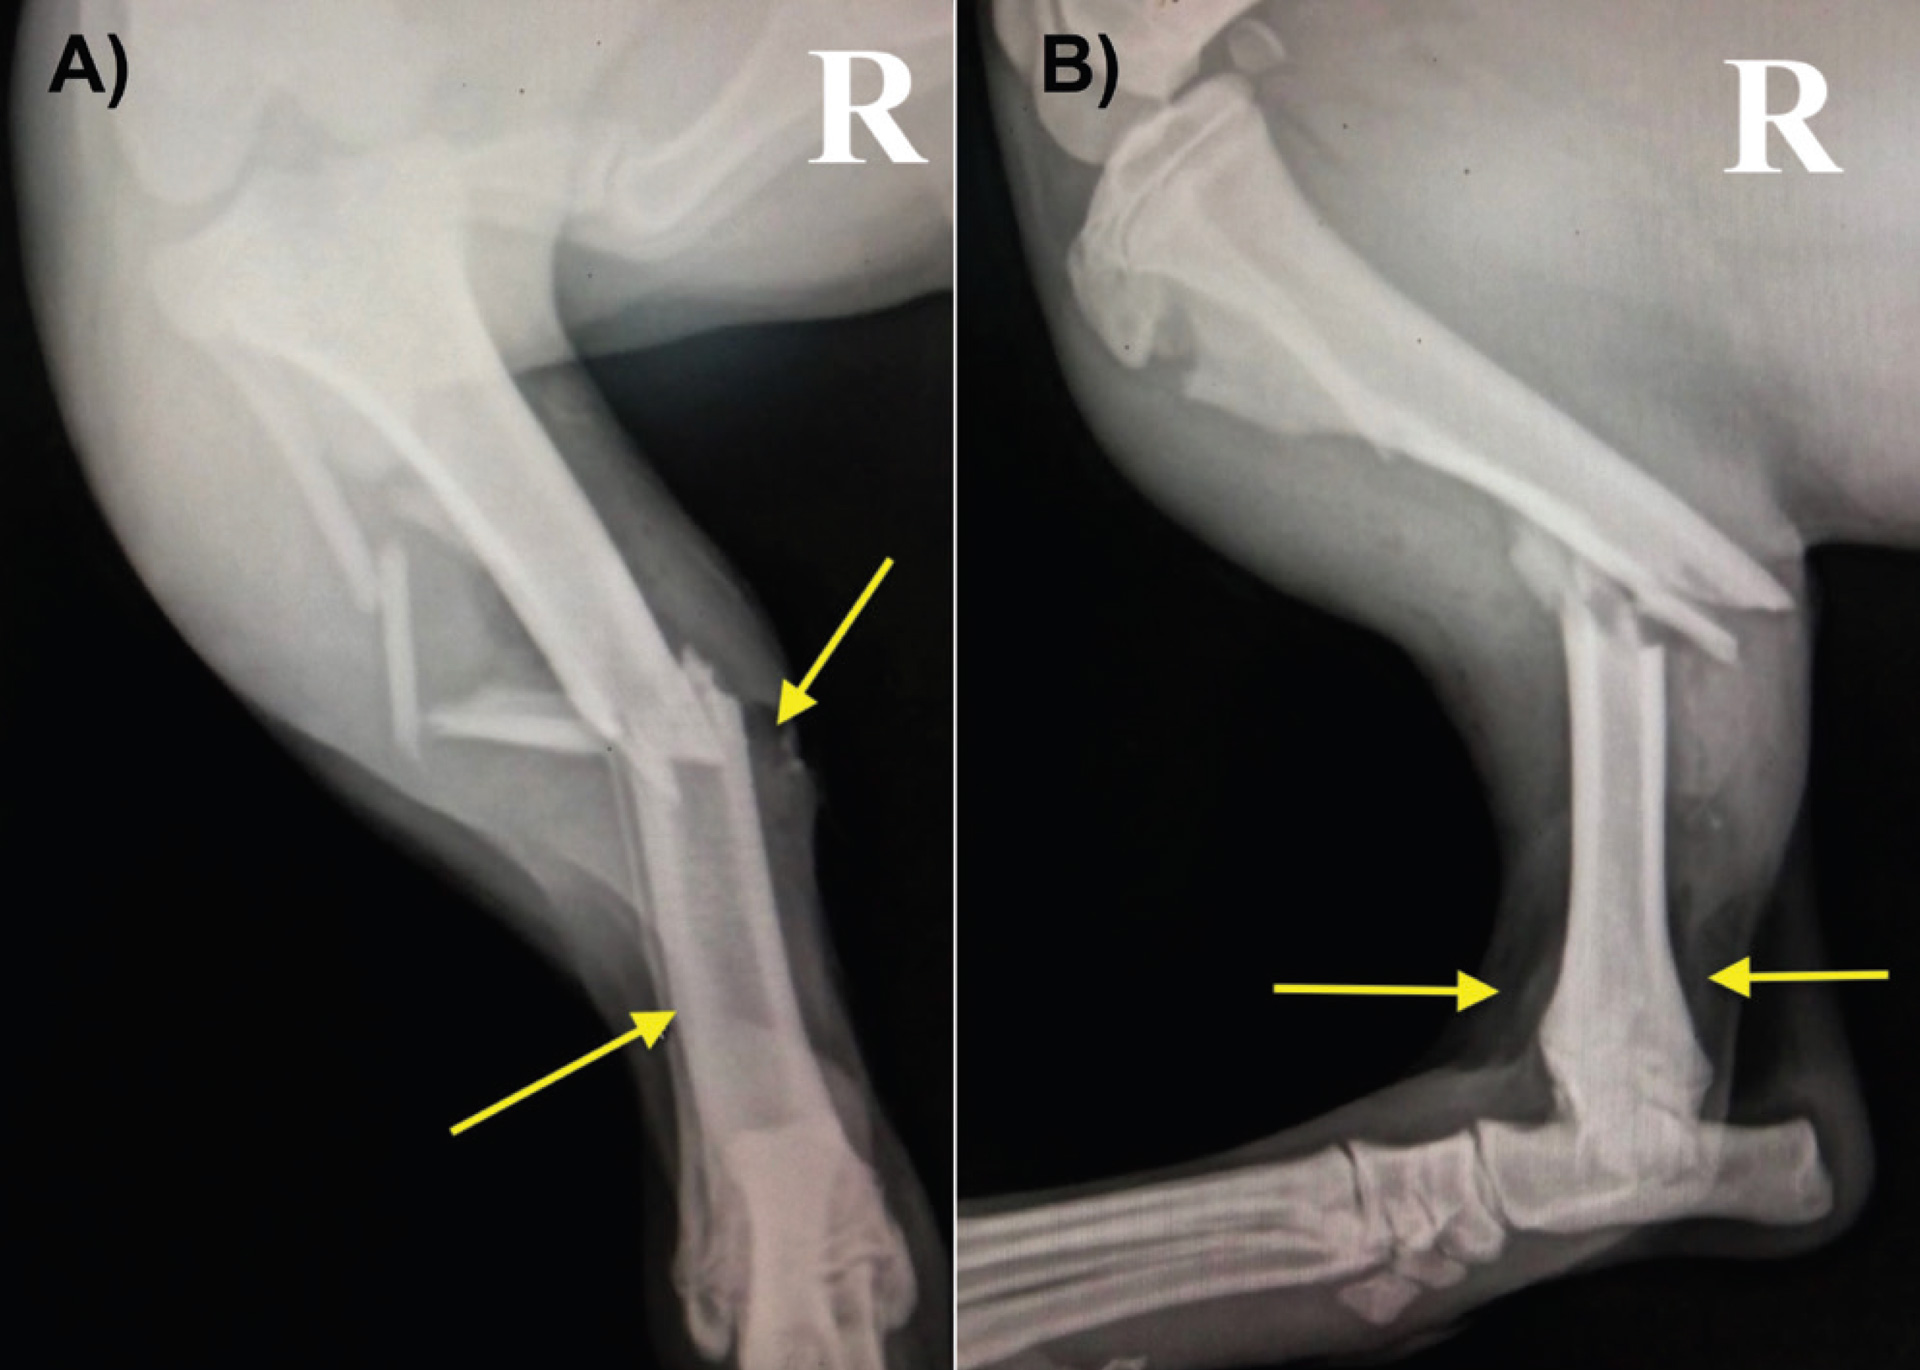

Figure 1: Examples of radiographic appearance of open fractures. A) Highly comminuted fracture in a feline patient affecting the proximal and distal diaphysis of the left tibia following a fall from a third floor. B) Left tibiotarsal mediolateral subluxation (view in neutral position) in a canine patient after a road traffic accident. The yellow arrows indicate gas accumulation under the skin due to soft tissue barrier disruption.

Figure 2: Examples of radiographic appearance of open fractures. A) Caudo-craneal and B) mediolateral radiographs of a comminuted fracture of the mid diaphysis of the right tibia in a five month-old canine patient after a road traffic accident. The yellow arrows indicate gas accumulation under the skin due to soft tissue barrier disruption.